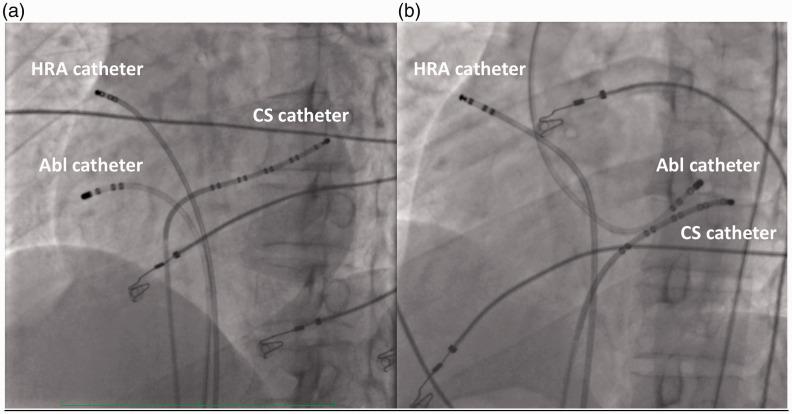

Mahaim 附加旁路解剖分布的综合评估。

Comprehensive assessment of Mahaim accessory pathways' anatomic distribution.

To present the authors' experience of Mahaim-type accessory pathways (MAPs), focusing on anatomic localizations.

Data from consecutive patients who underwent electrophysiological study (EPS) for MAP ablation in two tertiary centres, between January 1998 and June 2020, were retrospectively analysed.

Of the 55 included patients, 27 (49.1%) were male, and the overall mean age was 29.5 ± 11.6 years (range, 12-66 years). MAPs were ablated at the tricuspid annulus in 43 patients (78.2%), mitral annulus in four patients (7.3%), paraseptal region in three patients (5.5%), and right ventricle mid-apical region in five patients (9.1%). Among 49 patients who planned for ablation therapy, the success rate was 91.8% (45 patients).

MAPs were most often ablated at the lateral aspect of the tricuspid annuli, sometimes at other sides of the tricuspid and mitral annuli, and infrequently in the right ventricle. The M potential mapping technique is likely to be a useful target for ablation of MAPs.